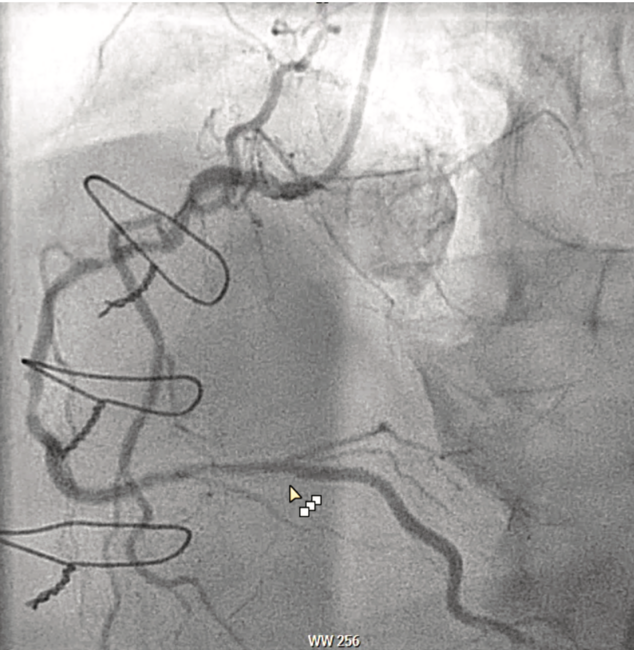

Coronary perforation during percutaneous transluminal coronary angioplasty (PTCA) occurs very rarely. However, with the recent availability of alternative devices that cut, tear, or ablate to improve luminal dimensions, perforations have been noted more frequently.1 Covered stents provide a physical barrier to seal perforated or ruptured large-vessel coronary arteries and reduce the risk of hemorrhage without the need for invasive surgery. We describe a case of a right coronary artery (RCA) perforation that was successfully treated using a polyurethane-coated (PK Papyrus) stent (Biotronik).